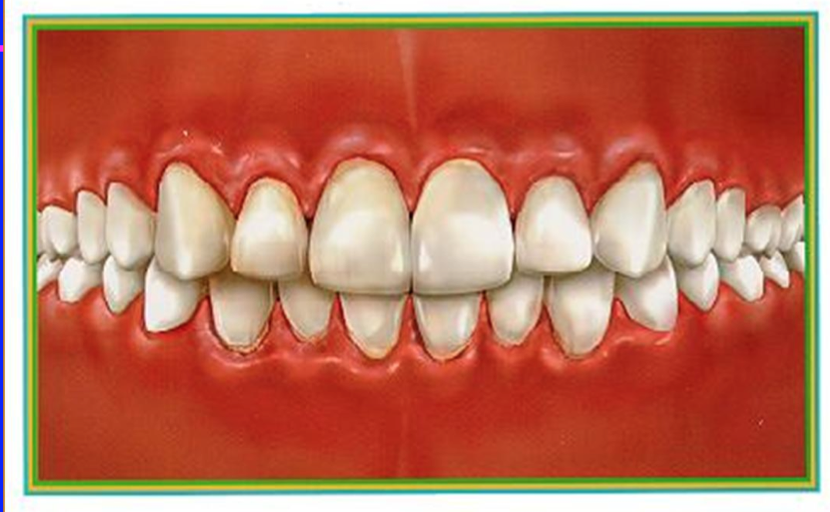

acute ulcerative gingivitis